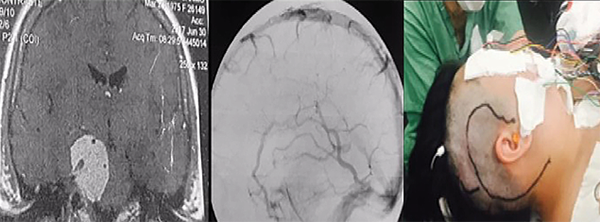

Los abordajes petrosos son pre-sigmoideo retrolaberíntico, pre-sigmoideo translaberíntico y petrosectomía total. Estos abordajes se utilizan cuando la lesión se encuentra en la fosa media, fosa posterior y la región clivus (Figuras 3 y 4). Si el paciente tiene buena audición previa, se prefiere el acceso pre-sigmoideo retrolaberíntico. Cuando no hay audición preservada es posible extirpar los canales semicirculares, y este abordaje se denomina pre-sigmoideo translaberíntico. Para los tumores gigantes que cruzan la línea media en la región prepontina es necesario un abordaje más lateral y extenso, a través de la petrosectomía total (petrosectomía posterior asociada con la petrosectomía anterior). La cirugía se realiza con el paciente en posición decúbito dorsal, con la cabeza vuelta hacia el lado opuesto. La incisión en la piel se realiza en forma semicircular a partir la región temporal, cuatro centímetros por encima del arco cigomático, pasando tres centímetros detrás de la oreja, extendiéndose dos centímetros detrás de la punta del mastoides. Para evitar fístula del LCR postoperatoria, se utiliza la reconstrucción de la base del cráneo con la fascia temporal, que se diseca con el periostio mastoideo, la fascia craneocervical y el músculo esternocleidomastoideo, que se separa de su inserción, formando un gran colgajo vascularizado que es girado para atrás al final de la cirugía para cubrir todo el campo quirúrgico. La corteza mastoidea es drenada, identificándose el laberinto y el canal del nervio facial. Estos canales no son abiertos. Se realizan dos trepanaciones por encima y dos por debajo del seno sigmoideo y, con una broca de alta rotación, se realiza una craneotomía, exponiendo las fosas media y posterior (retrosigmoide). Los senos petroso superior, sigmoideo y transverso son expuestos. Las celdas mastoideas retrofaciales se eliminan hasta el bulbo yugular. La duramadre anterior es expuesta al seno sigmoideo. Se extraen las células cigomáticas y supralaberínticas, manteniendo intactos los canales semicirculares y el oído medio. El seno petroso superior se secciona anterior a su entrada en el seno sigmoideo. Antes de esta maniobra, debe conectarse con un punto o con microclips. Luego, se realiza una incisión en el tentorio, inicialmente perpendicular al seno petroso superior de dos a tres centímetros y luego medialmente, paralelo al seno transverso en otros tres centímetros. Esta maniobra permite una amplia exposición del cerebelo, separándolo a partir del aspecto posterior del lóbulo temporal en "libro abierto". Se debe tener cuidado para preservar la vena de Labbé, que tiene una anatomía variable y generalmente ingresa al seno transverso diez milímetros antes de su unión con el seno sigmoideo. La evaluación preoperatoria de la anatomía venosa es esencial para planificar este abordaje. La incisión del tentorio se continúa hasta la incisión donde se expone y preserva el IV par craneal. Algunas pequeñas venas puente basales en la base anterior del lóbulo temporal se coagulan y cortan, permitiendo una amplia exposición subtemporal. Se debe evitar la colocación de espátulas fijas con Leyla apoyando el lóbulo temporal y el cerebelo. En general, la espatulación leve realizada por el auxiliar de manera no continua es suficiente para exponer toda la región petroclival de los pares craneales III a VII y VIII. El nervio trigémino generalmente se puede ver desplazado posterior y superiormente. El tumor se desvasculariza por la coagulación bipolar de su inserción dural. Posteriormente, la resección intracapsular fragmentada del tumor se realiza con un aspirador ultrasónico, realizando una citorreducción del tumor, que permite la disección de la cápsula tumoral de los nervios, la arteria basilar y las arterias cerebelosa superior y cerebral posterior. El nervio abducente es muy delgado y frágil. El canal de Dorello se encuentra medial a los pares craneales VII y VIII, y esta región debe abordarse solo después de una resección extensa del tumor. Las extensiones tumorales de la parte posterior del seno cavernoso se resecan después del nervio trigémino. Toda infiltración del hueso petroso y el clivus se elimina con una broca de diamante. Después de la extracción total, la duramadre se cierra herméticamente o con un injerto de fascia y pegamento de fibrina. El abordaje presigmoideo translaberíntico es similar, pero con la eliminación adicional del laberinto al drenar los canales semicirculares, lo que agregará una exposición de aproximadamente 1,5 centímetros de cirugía y permitirá una mejor vista de las estructuras de la línea media. Esta apertura de los canales semicirculares causa sordera y sólo está indicada para pacientes sin audición viable previa.1

Figura 3:Resonancia magnética con gadolinio, corte coronal, que muestra un componente tumoral en la fosa posterior y en la fosa media. Caso ideal para el abordaje petroso (izquierda). Angiografía de fase venosa que muestra drenaje de la vena de Labbé en la unión del sigmoide con el transverso, sin contraindicar el abordaje petroso (centro). Incisión del abordaje petroso (también conocido como abordaje presigmoideo (supra/infratentorial) utilizado en este caso (derecha).

Figura 4: RM coronal con gadolinio que muestra tumor con componente en la fosa posterior y en la fosa media. Caso ideal para el abordaje petroso, también conocido como petrosectomía posterior o abordaje presigmoideo supra/infratentorial (izquierda). Visualización del abordaje antes de abrir la duramadre (izquierda).